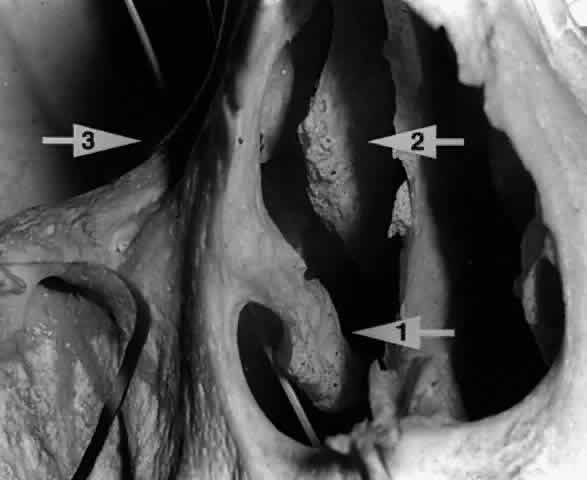

Sanderson and Stasior4 found islands of “peripheral” lacrimal glandular tissue below the lateral canthus unassociated with the main gland in 60% of cadaver specimens (Fig. 8). These peripheral islands of glandular tissue were found less commonly in or above the lateral canthal tendon.

Fig. 8. “Peripheral” lacrimal gland lobules (arrow 1) are seen below the right lateral canthus (arrow 2) and separate from the palpebral lobe of the lacrimal gland (arrow 3). (Courtesy of James Sanderson, MD, Orkan Stasior, MD, and George Stasior, MD)